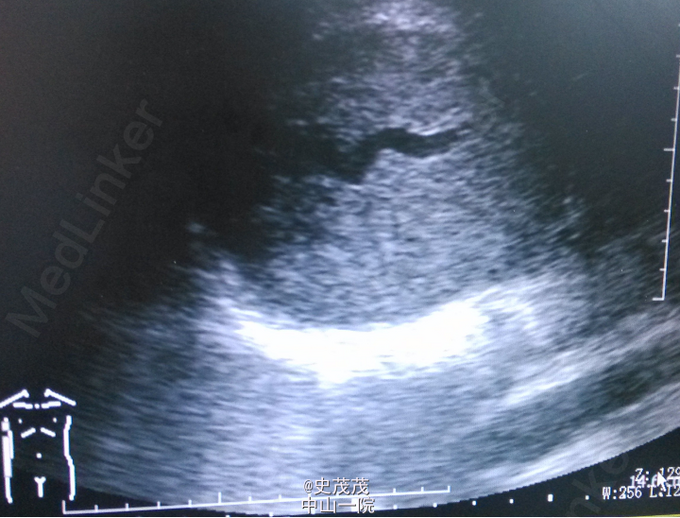

体格检查:心、肺(-)。腹平软,未见胃肠型及蠕动波。无压痛、反跳痛,未及腹部包块。肝脾肋下未及,Murphys’s sign (-),双中上输尿管点无压痛,肝、肾区无叩击痛,移动性浊音阴性。双肾区不饱满,肋腰凹存在,双肾未触及,为问及肾血管性杂音。双肾区、左侧输尿管行程区压叩痛(-)。膀胱区不膨隆,无压痛,叩诊鼓音,外生殖器无异常。 辅助检查:腹部B超示肝肾间隙范围约83×64mm低回声,边界请。彩色多普勒见血流信号。 腹部MR示右肾上腺区占位,约6.7cm×8.1cm×8.5cm大小,呈稍长T1、长T2信号,内部信号不均匀,可见斑片状明显长T1、明显长T2信号坏死区,DWI序列呈稍高信号,反相位肿块信号不减低。增强扫描,肿块呈明显不均匀强化,内部坏死区不强化,有渐进强化特征。考虑嗜铬细胞瘤可能。